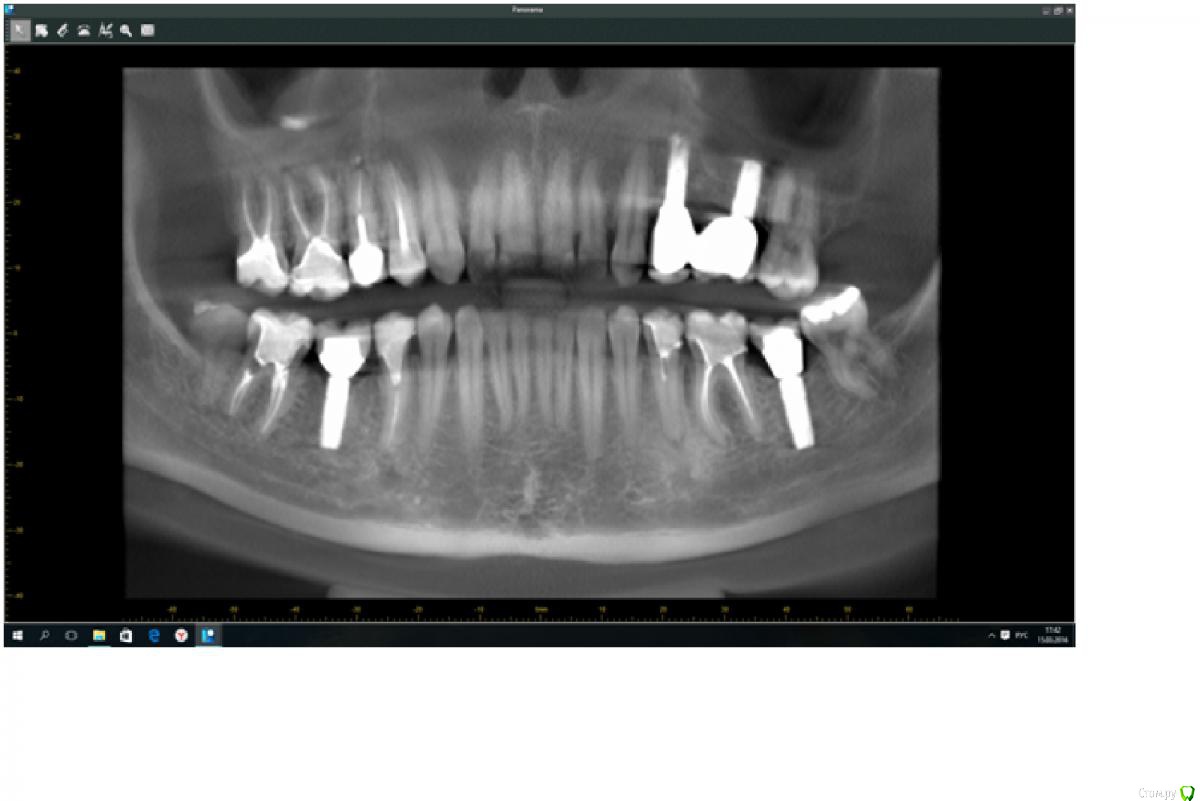

Anastasiya Neapoli Опубликовано 15 марта, 2016 Поделиться Опубликовано 15 марта, 2016 Добрый день, уважаемые врачи. Помогите пожалуйста советом. Испытываю боль при жевании и особенно после нагрузок (спортивных) на правой стороне. Идет пульсация и нарастающая боль, которая проходит через какое то время, заметила, что проходит после чистки зубов и обработки ирригатором. Иногда такая реакция происходит на горячее или холодное. Определить конкретный зуб не могу. По ощущениям это вроде верхний ряд. Боль начинается от зуба и в висок и глаз, иногда пью обезболивающее. Была у стоматолога, он холодным воздухом "продувал" и верхний и нижний ряд, так же нагревал. И у него в кабинете чувствительности не обнаружилось. Думала на восьмерку верхнюю удалили ее, но боль осталась. Карманы доктор говорит навряд ли. На четверке верхней правой старая коронка и на корне гранулема. Но доктор говорит не даст такой болевой синдром она. Прилагаю панораму, скрин из КТ, сделала недели две назад. Ссылка на комментарий

red_butler Опубликовано 16 марта, 2016 Поделиться Опубликовано 16 марта, 2016 Пробу холодом нужно проводить с использованием хладагента, нужен очный осмотр. Если судить по снимку, то перелечивать 4,5,6 и седьмой зубы на верху справа и удалять мудрый зуб снизу. 1 Ссылка на комментарий

red_butler Опубликовано 16 марта, 2016 Поделиться Опубликовано 16 марта, 2016 Спасибо за комментарий. А по подробнее по поводу 4,5,6,7 справа сверху. Они кроме пятерки лечены два года назад всего. Стоят вкладки керамические. Что с ними? А что с восьмеркой. Стоматологи что смотрели очно не нашли в нем проблемы.. Расскажите пожалуйста по подробнее.1.6 1.5 периодонтит, 1.7 1.4 плохо видно, но похоже тоже не спокойно. 3.5 3.6 так же периодонтит.Восьмой зуб лишен антагониста и полноценно не участвует в жевании. Ссылка на комментарий

IvanK Опубликовано 17 марта, 2016 Поделиться Опубликовано 17 марта, 2016 Я добавила снимок. Посмотрите пожалуйста.очный осмотр важен в Вашем случае + Ваш скрин не дает полной информации предположить могу, что симптомы Боль начинается от зуба и в висок и глаз,связаны с 48 Испытываю боль при жевании заметила, что проходит после чистки зубов и обработки ирригатором.скорее всего контактные пункты между зубами не очень хороши , пользуетесь зубной нитью? согласен с Коллегой, что 15 и 16 - периодонтиты, Ссылка на комментарий